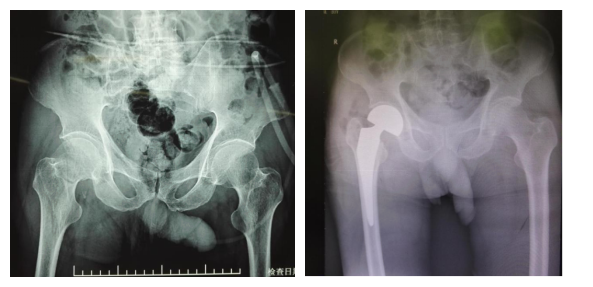

该患者因其他疾病在外院住院,住院期间不慎跌倒伤左右髋部,拍片显示:右股骨颈骨折。随后转入我科进一步治疗。转入后检查发现该患者同时合并高血压、肺部感染、前列腺增生并泌尿系感染、贫血等多种内科疾病,这一系列并发症及既往史都给手术带来了前所未有的风险和考验。

患者入院后经科室积极治疗,待血压控制平稳,肺部感染及泌尿系感染得到有效控制后,经过与患者及家属详细沟通,患者和家属同意接受手术治疗。在科室陈跃平主任及陈涛副主任的带领下,综合考虑患者的身体条件后最终决定采用创伤小、恢复快的DAA微创人工髋关节置换术,整个手术过程持续时间90分钟,对周围组织剥离少,术中出血只有150ml。目前该老人康复良好。

术前(左)与术后(右)对比图